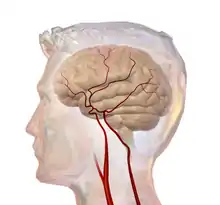

Cerebral circulation is the movement of blood through a network of cerebral arteries and veins supplying the brain. The rate of cerebral blood flow in an adult human is typically 750 milliliters per minute, or about 15% of cardiac output. Arteries deliver oxygenated blood, glucose and other nutrients to the brain. Veins carry "used or spent" blood back to the heart, to remove carbon dioxide, lactic acid, and other metabolic products. The neurovascular unit regulates cerebral blood flow so that activated neurons can be supplied with energy in the right amount and at the right time.[1] Because the brain would quickly suffer damage from any stoppage in blood supply, the cerebral circulatory system has safeguards including autoregulation of the blood vessels. The failure of these safeguards may result in a stroke. The volume of blood in circulation is called the cerebral blood flow. Sudden intense accelerations change the gravitational forces perceived by bodies and can severely impair cerebral circulation and normal functions to the point of becoming serious life-threatening conditions.

Blood supply to the brain is normally divided into anterior and posterior segments, relating to the different arteries that supply the brain. The two main pairs of arteries are the Internal carotid arteries (supply the anterior brain) and vertebral arteries (supplying the brainstem and posterior brain).[2]. The anterior and posterior cerebral circulations are interconnected via bilateral posterior communicating arteries. They are part of the circle of Willis, which provides backup circulation to the brain. In case one of the supply arteries is occluded, the circle of Willis provides interconnections between the anterior and the posterior cerebral circulation along the floor of the cerebral vault, providing blood to tissues that would otherwise become ischemic.[3]